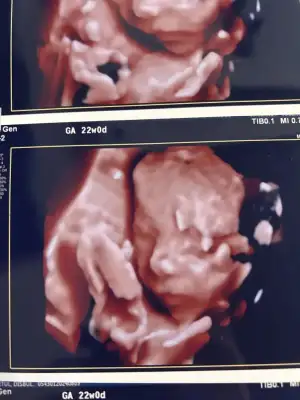

Güzel kızlar eklesin pozumuz ektedir bu arada 😂